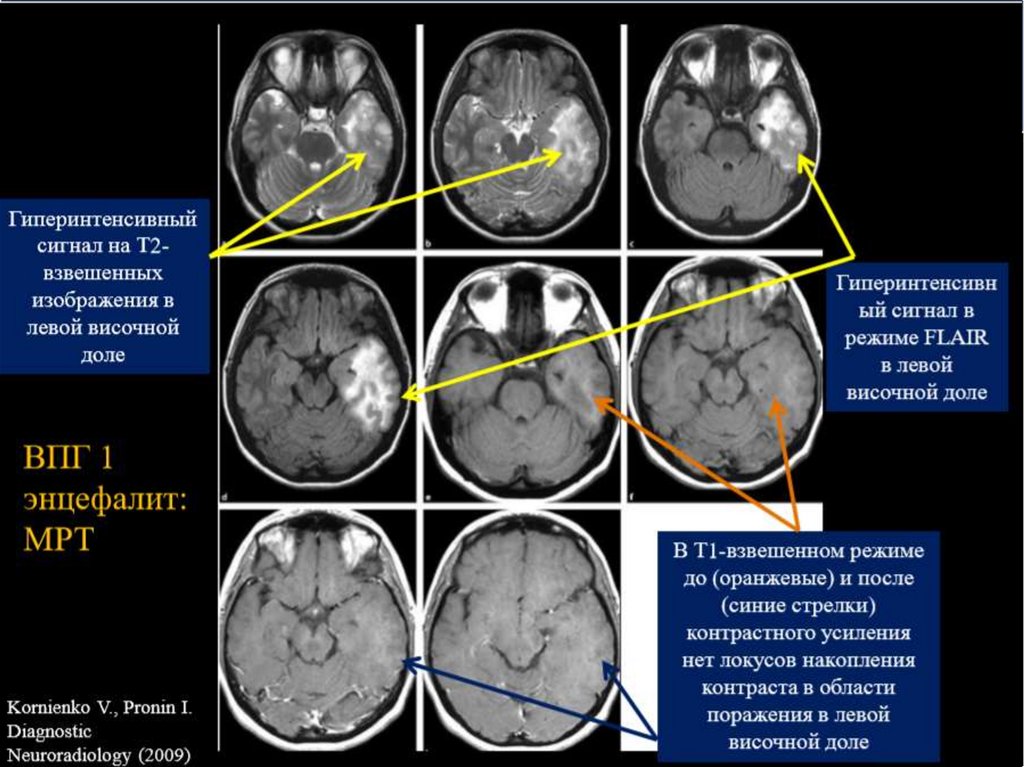

2. Энцефалит

Энцефалит — это воспаление головного мозга, часто вызванное вирусной инфекцией. Симптомы могут включать:

— Лихорадку

— Головные боли

— Спутанность сознания и судороги

Состояние может быть опасным для жизни и требует незамедлительного медицинского вмешательства. Лечение направлено на устранение причины и поддержку функций мозга.

Магнитно-резонансная томография (МРТ) и компьютерная томография (КТ) являются основными инструментами для визуализации структуры мозга и спинного мозга. Эти методы помогают в выявлении опухолей, воспалительных процессов и других патологиях.